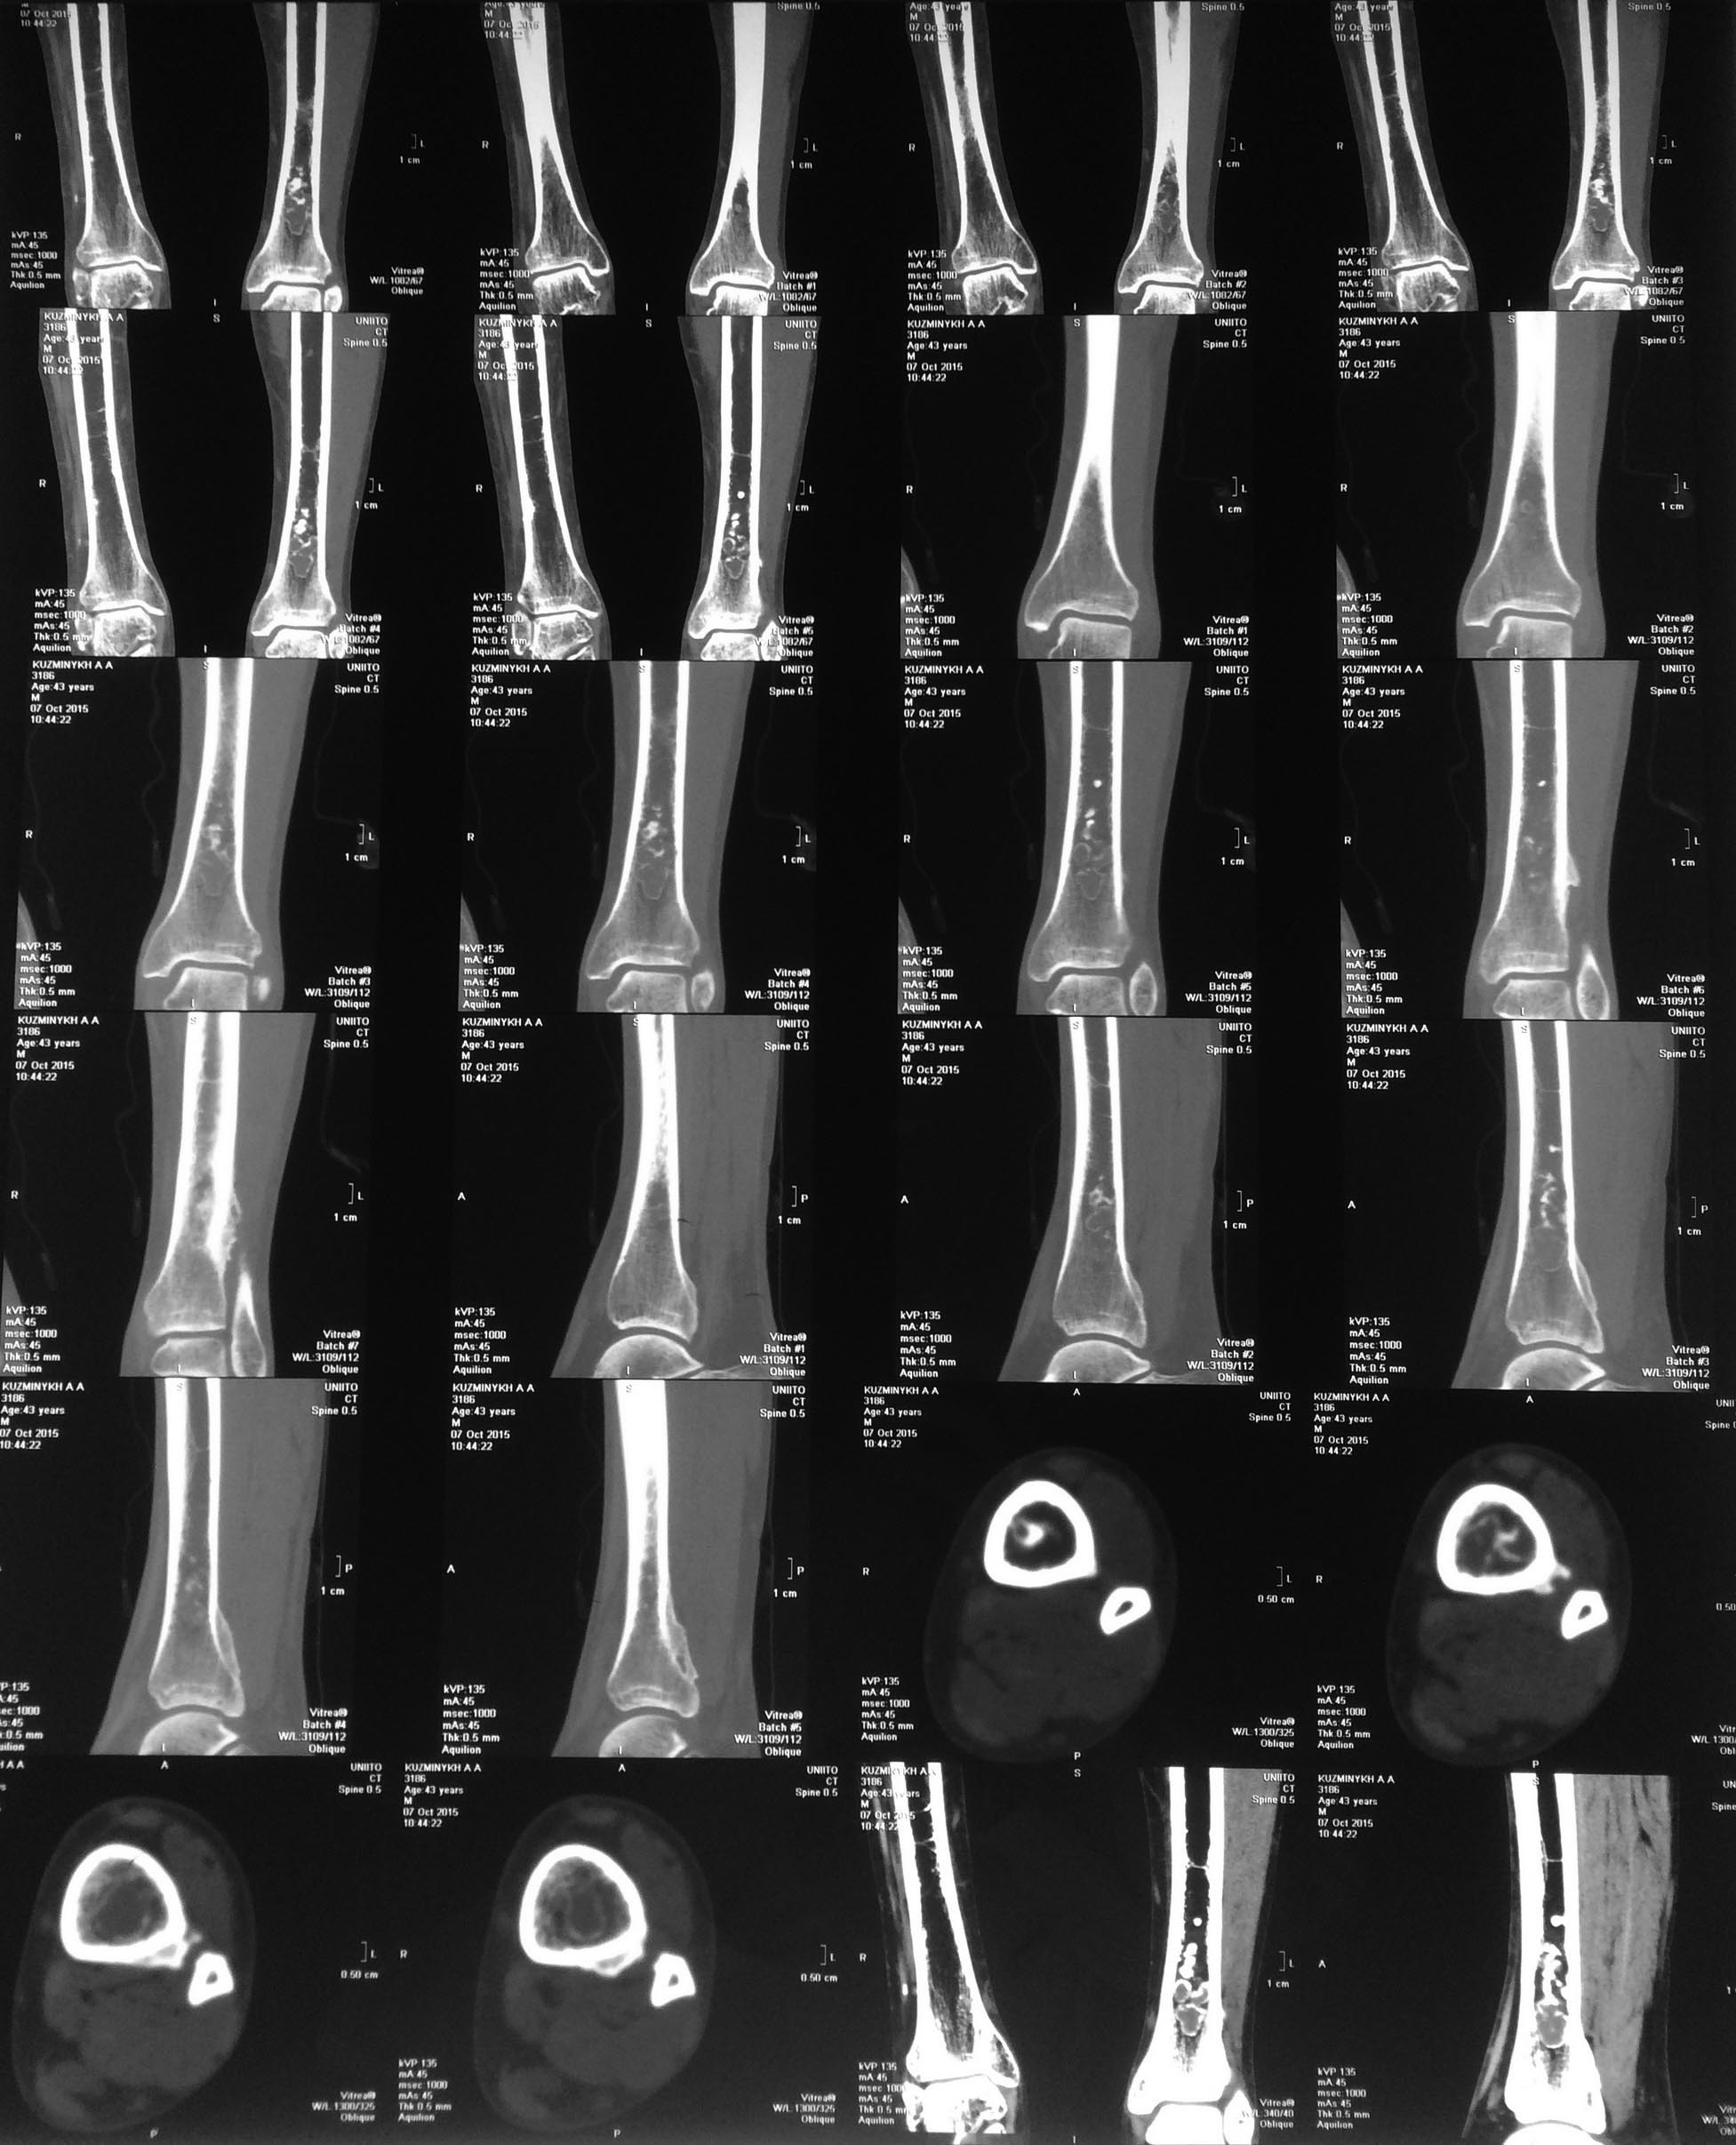

Хондромиксоидная фиброма

Доброго времени суток, уважаемые коллеги!В клинику поступил пациент 43 лет с жалобами на боли в области левой голени.

Боли постоянные, ноющего характера, резко усиливаются при ходьбе, а также при согревании конечности.Появились боли около года назад, сперва незначительные, но резко усилились в течение последних 3 месяцев.

Объективно - кожные покровы и мягкие ткани голени и стопы не изменены. При пальпации болезненных ощущений не испытывает. Отмечает болезненность при поколачивании по гребню большеберцовой кости. Движения в голеностопном суставе без ограничений, умерено болезненные.

Согласно результатам КТ от 7.10.15 рентгенологами установлен диагноз:" Ходромиксоидная фиброма левой голени".

Уважаемые коллеги! Просим Вашего совета в отношении дальнейшей тактики ведения пациента. Какой объём хирургического вмешательства применить? С учётом того, что по данным многих авторов подобное новообразование имеет большую склонность к рецидивам (до 40%), какой пластический материал для замещения пострезекционного дефекта предпочтительнее?

Хондромиксоидная фиброма--крайне редкое явление. Да и выглядит она не так, как этот случай. Она находится не по центру кости. Я буду очень удивлён, если этот диагноз подтвердится. Я работал с радиологом, специалистом по опухолям кости, который говорил, что хондромиксоидная хондрома встречается так редко, что если о нём 10 лет ни разу не упоминал, то всё впорядке. Ваш случай больше похож на остеомиелит, энхондрому или хондросаркому, или же на остеонекроз. Надо начать с анализов крови для проверки на инфекцию и биопсии. Ткань с биопсии пошлите на бактериальный посев. А по результатам биопсии решайте, что делать дальше.